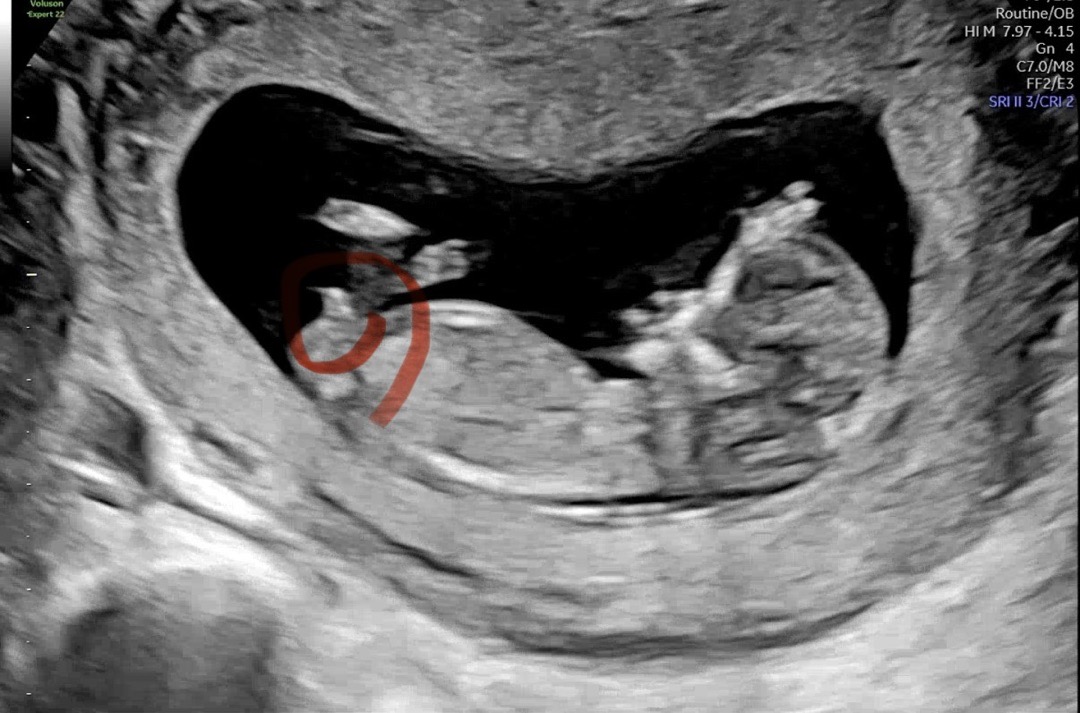

11주5일 성별 투표해주세용

투표부탁두립니다!